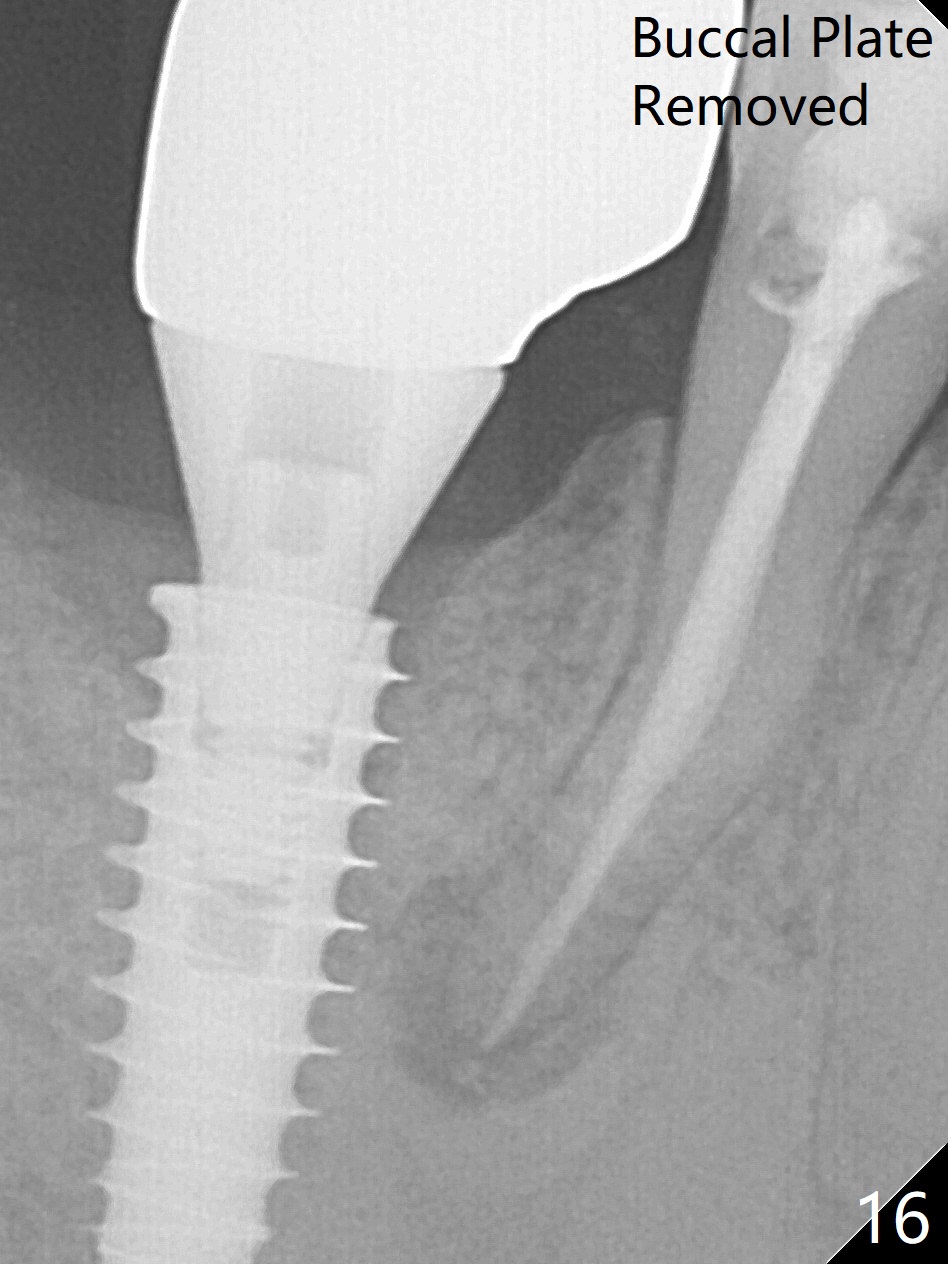

Bone graft seems to sink down and becomes denser 3 months postop (Fig.6 arrow). The bone continues being denser 5 months postop (Fig.7). There is periapical radiolucency of the tooth #29 (^). RCT is done (Fig.8). The pain persists 2 weeks postop (Fig.9,10). There is no missing canal (Fig.9). The apex is close to the implant (Fig.9 *). Apicoectomy will be performed if needed. It appears that the implant is also placed buccal (Fig.10 <) and/or the implant too large for the site. Therefore there should be a 2-3 mm buccal gap before and after implant placement. Separation and reflection of the buccal flap allows better visibility. The pain persists 1 month post RCT and 6 months post implant placement. RCT retreatment is initiated (Fig.11,12) with placement of Calcium Hydroxide paste after redebridement with 30/.04 rotary file at 23.5 mm (.5 mm longer than the earlier RCT, Fig.13). RCT retreatment finishes with apparent transportation and extrusion in 4 weeks (Fig.14,15), followed by apicoetomy (Fig.16,17) (20 days later)). Discomfort remains 2.5 months postop (Fig.18). Keep watching.